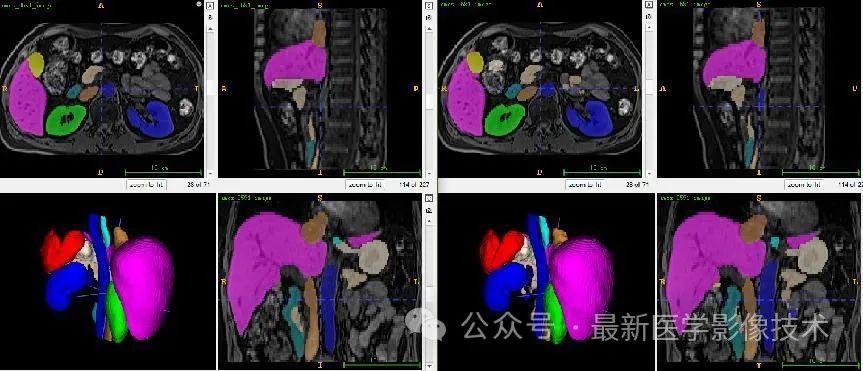

13、测试集分割结果